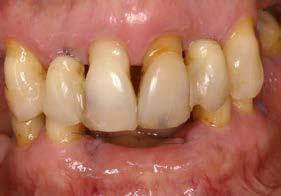

Figuras 2-3. Imágenes intraorales que evidencian pérdida ósea generalizada, extrusión de dientes anteriores y recesiones en todas las piezas presentes.

Se presenta el caso de una mujer de 65 años con diagnóstico de periodontitis severa al inicio del tratamiento. El examen clínico evidenció pérdida

Figura 1. Radiografía panorámica inicial que muestra la enfermedad periodontal avanzada de la paciente, con ausencia de varias piezas dentales y otras de mal pronóstico.

Implantes y propiocepción: la importancia de preservar dientes clave en pacientes con enfermedad periodontal avanzada

ósea vertical generalizada, defectos angulares en sectores posteriores y múltiples ausencias dentarias en ambos maxilares. La inspección intraoral mostró recesiones gingivales, exposición radicular y colapso del tercio anterior como consecuencia de migración dentaria y pérdida de soporte (Figura 1-3).